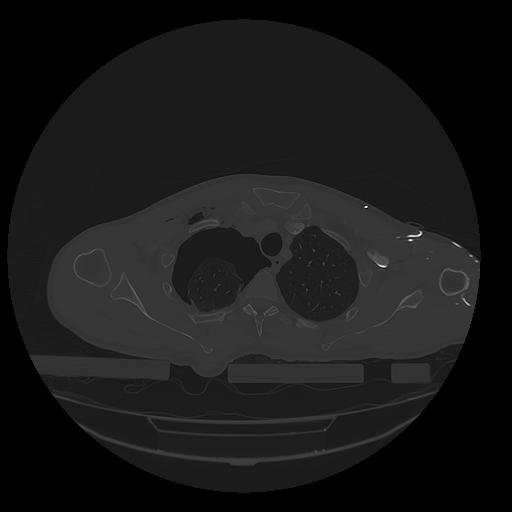

31 PULMON,CE,Vol,1.0,PULMON,,